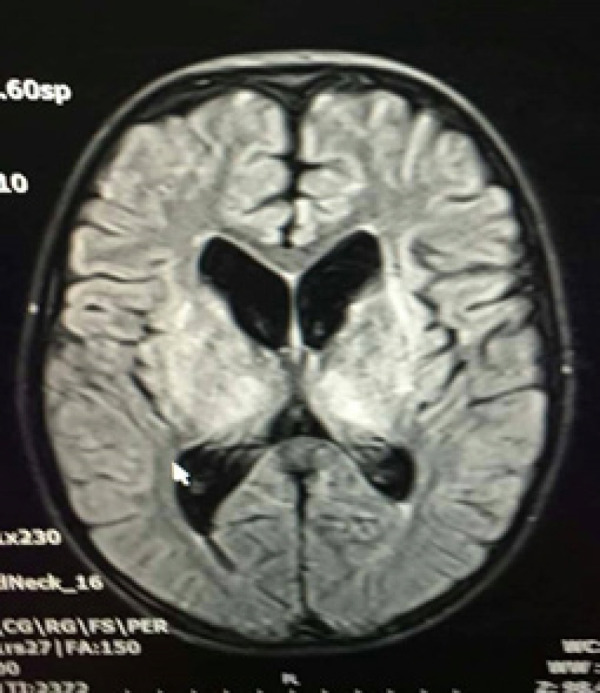

威尔逊病是一种以铜在各器官积累为特征的遗传性疾病,根据沉积部位的不同,导致广泛的临床表现。肝豆状核病的典型症状出现在5岁至35岁之间,主要表现为神经和肝脏症状。本病例报告描述了一名12岁男孩,根据低血清铜蓝蛋白水平和24小时尿铜水平升高诊断为威尔逊病。他最初的表现包括急性脑病和持续低钾血症的小管病。该病例强调了全面评估的重要性,包括神经和肾脏评估,以确定急性脑病(如Wilson病)的潜在病因。此外,本病例显示肝豆状核变性可表现为神经系统和肾脏表现,尽管肝脏评估正常。

Wilson disease is an inherited disorder characterized by copper accumulation in various organs, leading to a wide range of clinical manifestations depending on the deposition site. Typically, symptoms of Wilson disease emerge between the ages of 5 and 35 years, primarily presenting with neurological and hepatic symptoms. This case report describes a 12-year-old boy diagnosed with Wilson disease based on low serum ceruloplasmin levels and elevated 24-hour urinary copper levels. His initial presentation included acute encephalopathy and tubulopathy with persistent hypokalemia. This case highlights the importance of a thorough evaluation, including neurological and renal assessments, to determine the underlying cause of acute encephalopathy, such as Wilson disease. Furthermore, this case shows that Wilson disease can manifest with neurological and kidney presentations despite a normal hepatic evaluation.